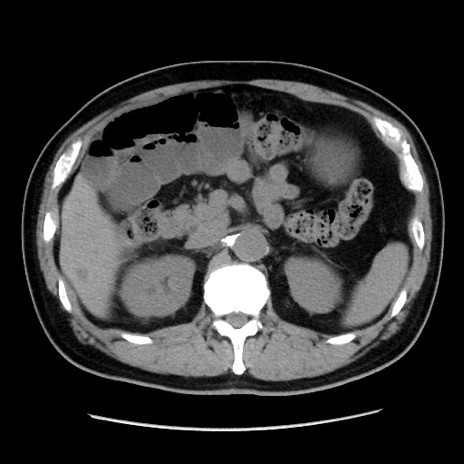

症例16(横断像)

【症例】 70歳代男性

【主訴】 腹痛、嘔吐

【現病歴】 約1ヶ月前より間欠的に腹痛と嘔吐あり、当院消化器内科を受診したところCTで多発する肝臓のLDAを指摘され、精査中であった。以降は消化器症状は安定していたが、2日前より嘔気と腹痛があり、同日より排便・排ガスが消失した。改善認めず、 本日、救急外来を受診した。

【既往歴】 大腸ポリープ切除後。

【身体所見】意識清明・会話良好、BT 36.3℃、BP 127/80mmHg、 P 80bpm、腹部:膨満あり、平坦・軟、上腹部正中および下腹部正中に圧痛あり、反跳痛なし、筋性防御なし。

【データ】WBC 7200、CRP 0.77